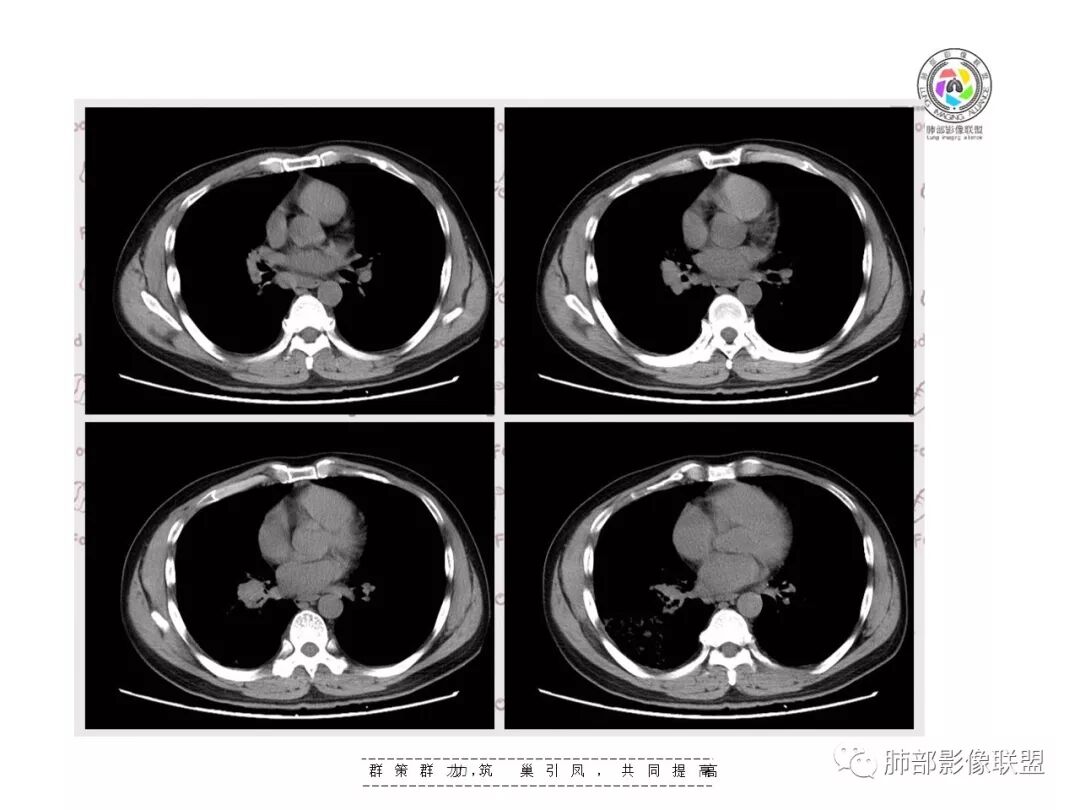

复查胸部CT视频显示肺部病灶明显吸收,淋巴结较前缩小。

患者在本院做了支气管镜,报告是有新生物,取了活检就转院了。病理结果是后来出来的。去肿瘤医院再做支气管镜,病理还是炎症。抗炎治疗(电话追问患者家属,具体不详)一个月后复查,右下肺病变基本吸收,肺门肿块明显变小;纵隔淋巴结基本都没了或者明显变小了

一个月吸收,不是快,是慢,合并机化可能。结核肯定不是。只是觉得你们早上不看病史。有点不好,至少抗感染复查。

现在看树雾,支原体有可能。只是淋巴结肿大和体重减低有迷惑性

如果TB不可能吸收这么快

对,支原体要考虑